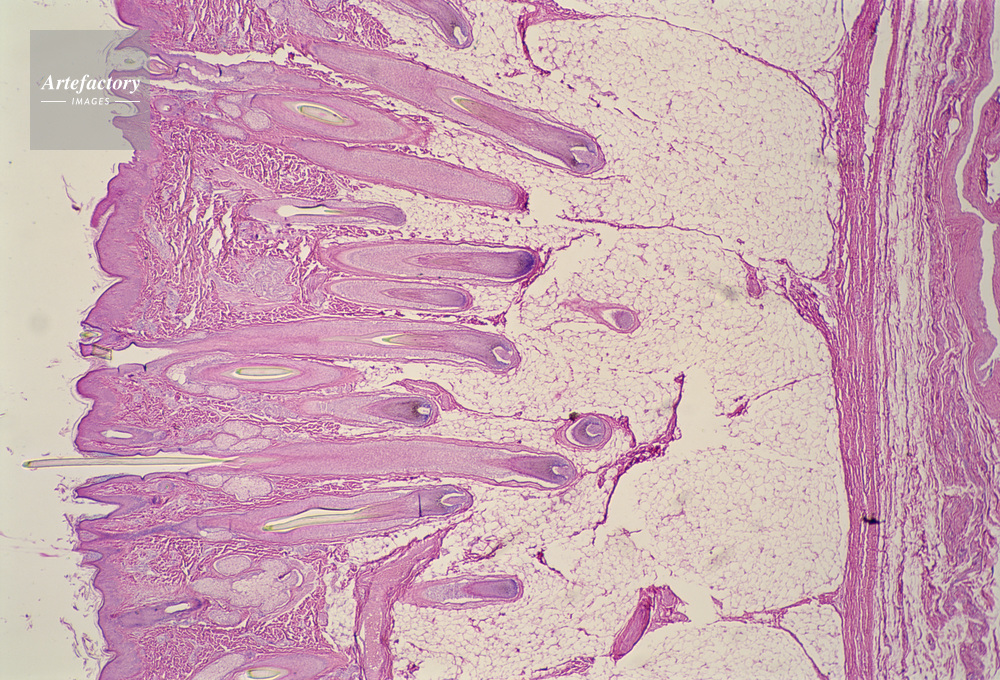

| キャプション | 頭皮毛幹,人間,10倍 | 制限事項 | ||

| ソース | ピクセル数 | 5554px × 3777px | ||

| 撮影地 | 印刷サイズ | 30.3cm × 20.6cm | ||